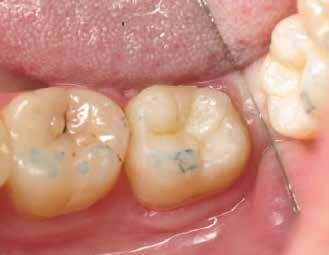

2. ábra: A páciens egy nem megfelelő I. osztályú ezüstamalgám töméssel és II. osztályú szuvasodással jelentkezett. A fog izolálása kofferdám alkalmazásával történt.

3. ábra: A preparálás, a bondozás és a kompozit felvitele után. (Megjegyzés: némi kompozit túlfolyás látható a mesiális doboz axiális falain).

4. ábra: A durva finírozás után a restauráció pereme sima és anatómiailag is megfelelő.